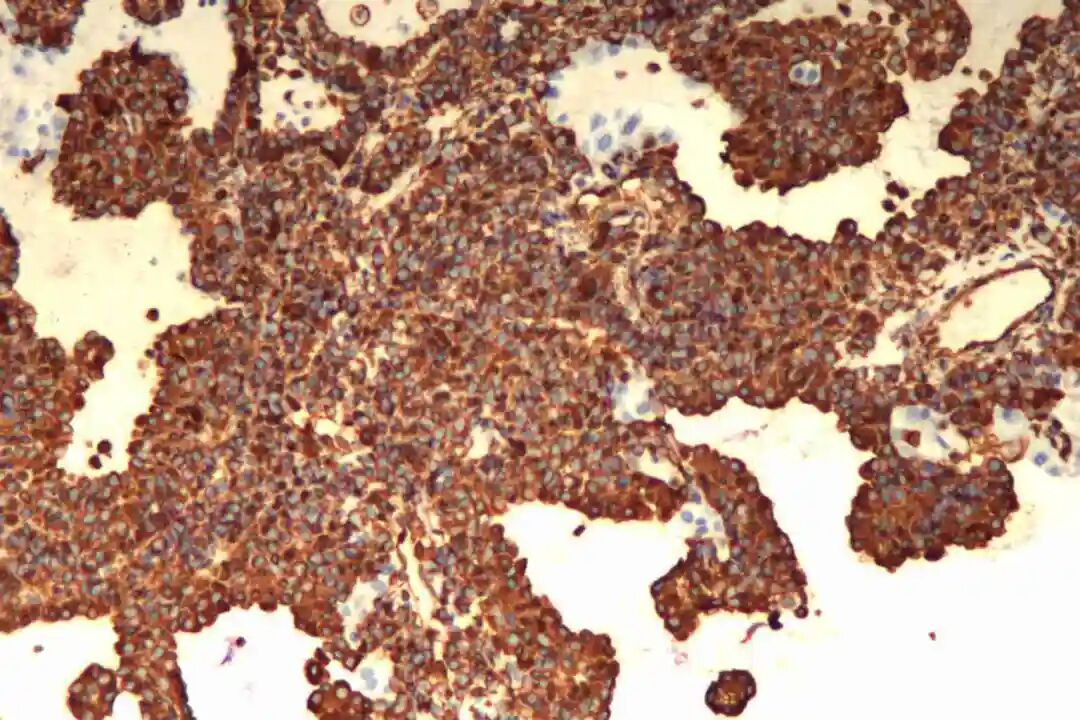

免疫组化:表面细胞:CKpan(+),TTF-1(+),NapsinA(+),EMA(+),Vimentin(+),CK7(+),CD56(-),Ki67(5%+);间质细胞:TTF-1(+),EMA(+),Vimentin(+)。